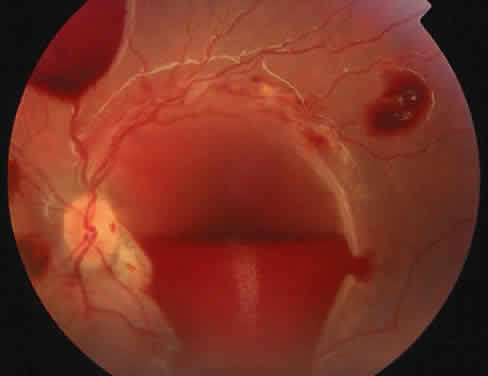

The ocular manifestations of antiphospholipid antibodies include retinal venous and arterial occlusions, amaurosis fugax, diplopia, and visual field loss.34,35 Extensive vasoocclusion, neovascularization, and vitreous hemorrhage may occur (Fig. 3). Treatment consists of photocoagulation for the neovascularization and systemic anticoagulation and immunosuppression. Vitrectomy may be required for vitreous hemorrhage. The role of systemic treatment of lupus anticoagulant in the management of ocular disease is unclear. Some investigators suggest that systemic anticoagulation be started promptly.36 The optimal duration of anticoagulation and whether antiplatelet therapy should be used are not known however. The optimal use of corticosteroids or other immunosuppressive drugs such as cyclophosphamide and azathioprine also is unknown. Two reports have found an association with the antiphospholipid syndrome and some additional retinal conditions. One report also has associated the primary antiphospholipid syndrome with central serous chorioretinopathy.37 In addition, lupus anticoagulant positivity could represent an additional risk factor for diabetic retinopathy according to a recent report.38